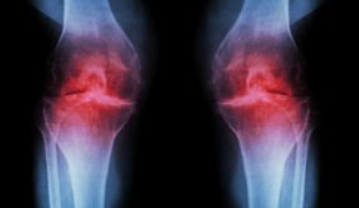

2. 관절염

정의: 무릎 관절의 염증성 질환입니다.

발생 원인: 나이, 유전, 체중, 이전의 부상 등 여러 원인에 의해 발생할 수 있는 무릎 안쪽 통증 원인입니다.

예방 및 관리: 정기적인 운동, 체중 관리, 통증을 줄이는 약물 치료 등이 있습니다.